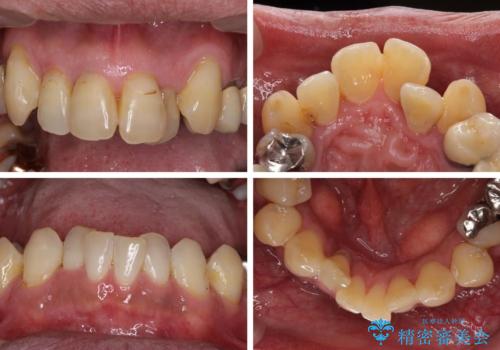

- 前歯がのデコボコや、奥歯に咬んだときに痛みがあるとのことで来院された患者様です。

全体的に問題が多く、全てをしっかりと治療したいとのことでした。

全体的に中等度の歯周病と診断されたため、歯周外科処置やインプラントによる咬合回復から進めて行き、矯正治療による歯列改善を行った後にオールセラミッククラウンにて補綴することとしました。

歯槽骨の再生治療を行ったため、外科処置後の静置期間がながくなり、4年弱の治療期間となりました。

初診来院時には矯正治療を行うことは想像していなかったようで、治療後には咬みやすさだけでなく、前歯が大変審美的に仕上がり、患者様には大変満足していただきました。